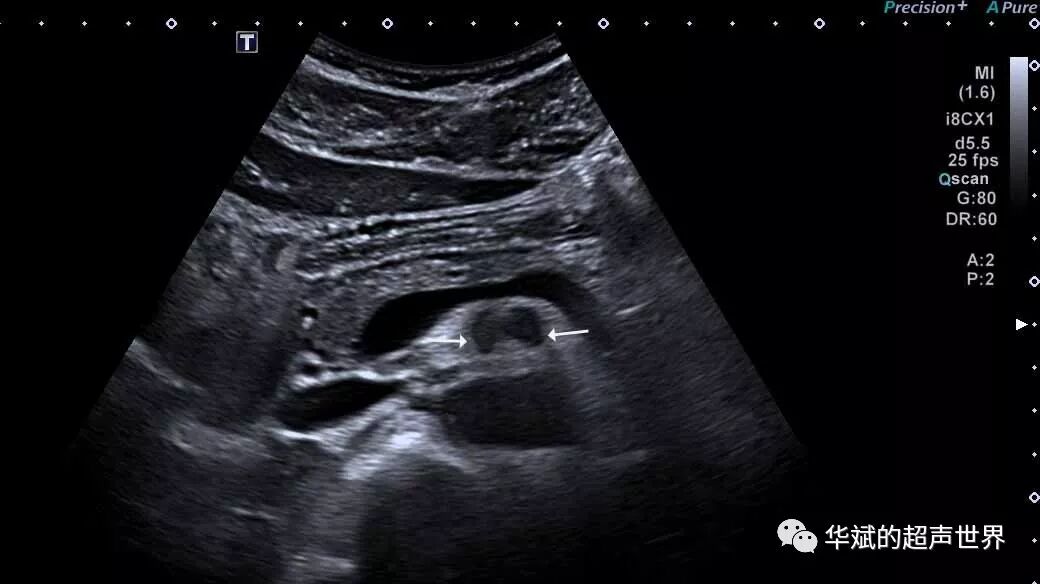

折射伪像最经典的例子就是腹直肌构成的所谓“棱镜效应”。超声波经过棱镜一样的腹直肌时发生显著折射,使得深方的结构出现所谓的重复伪像。(图1,图2所示)

图2 腹直肌棱镜效应导致深方的肠系膜上动脉出现“重复伪像”。注意更深方的腹主动脉也被横向拉宽,同样也是重复伪像。